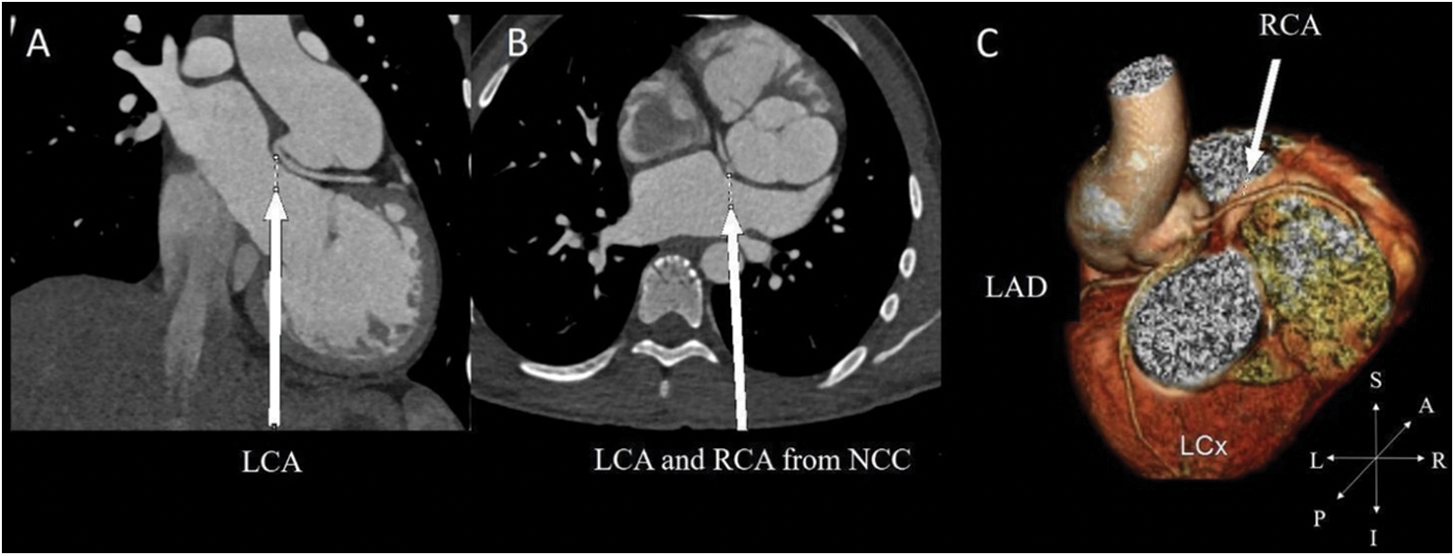

Among subjects with a single coronary artery and common ostium of the RCA and LAD 60% (6 out of 10 patients) reported multiple episodes of chest pain (all symptomatic patients also had prepulmonic course of coronary artery after ASO), compared with 9% (3 of 33 cases) of patients with other coronary artery patterns (adjusted OR = 14.3%, 95% CI (2.5–82.3); P = 0.003) (Table 4). Of those who have preoperative unusual coronary patterns, prepulmonic course was found in 11 (55%) patients including 1R-2LCx, 1RL-2Cx, 1RLCx, and 2LCxR (Figs. 2 and 3). Six of 11 (54%) patients in this group experienced significant chest pain (crude OR = 11.6%, 95% CI (2.1–62.2), P = 0.001). Interarterial courses were seen in nine patients (20%), and two of those patients reported significant chest pain (22%). Among them, seven patients had an interarterial course of LAD or LMCA, while two patients had an interarterial course of RCA (Fig. 4). Acute take-off angle occurred in three patients (6.9%); each had high take-off (coronary ostia located above the sinotubular junction) [29], but none had significant coronary stenosis (Fig. 5). The mean aortic root z score in patients post-ASO was 4.71 ± 2.4 [30].

Figure 5: In a patient with preoperative 2LCxR pattern. (A) Acute take-off angle of LCA in the coronal. (B) The LCA and RCA arise from noncoronary cusp (NCC) as reimplantation site in the axial view. (C) 3-dimensional reconstruction of coronary distribution